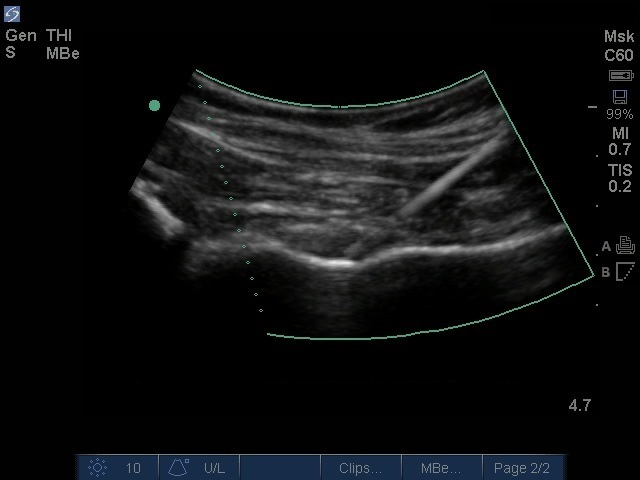

Imagen de inyección en cadera con tecnología mejorada de la aguja curvilínea